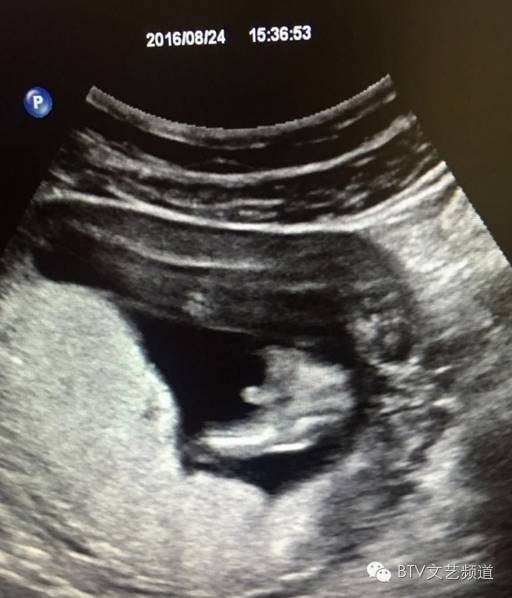

没想到就在今天,孙茜就在微博晒出B超照宣布怀孕,同时还晒出自己和丈夫的童年照,感慨:“三年,三个人,三颗心,谢谢生命的力量”。